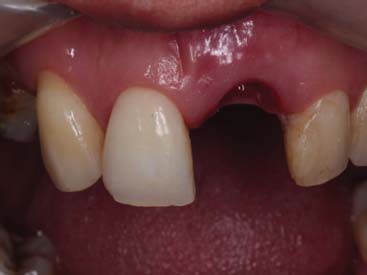

A paciente ERL, gênero feminino, 28 anos, procurou atendimento relatando dor na região anterior superior, com histórico de trauma prévio durante a mastigação. Na avaliação da paciente, o dente 21, aonde havia uma coroa cerâmica instalada com núcleo metálico, apresentava uma fratura obliqua, gengiva edemaciada, com sinais clínicos de infecção na parede vestibular do alvéolo (figura 1 e figura 2). O plano de tratamento incluiu a indicação de exodontia do dente 21, seguida de um implante imediato (Straumann® Bone Level SLActive) associado a um cicatrizador personalizado para manter a caracterização do contorno gengival do elemento.